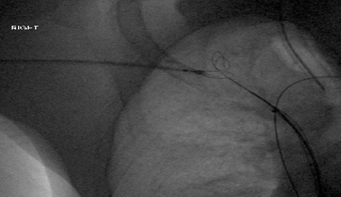

1. Access Points: Simultaneous transjugular (upper extremity, representing the pressurized or downstream segment relative to the heart) and transfemoral (lower extremity, typically the upstream, access-only segment) catheterization were utilized to exactly define the extent of the occlusion and create two “targets” for the sharp needle.

2. Recanalization Tool: A specialized BRK1 needle was specifically used. This type of needle is commonly employed in transseptal puncture in cardiology, highlighting its design for precise, intentional perforation of tough, fibrotic tissue.

3. Guidance: The recanalization was performed under meticulous triangulation fluoroscopy, guiding the sharp needle from the downstream territory (often the femoral side, moving cranially) toward the pressurized upstream territory (the jugular side, moving caudally, or vice-versa depending on the occlusion site). This controlled transgression minimizes the risk of cardiac or mediastinal injury. The two accesses allow for controlled entry and exit points.3